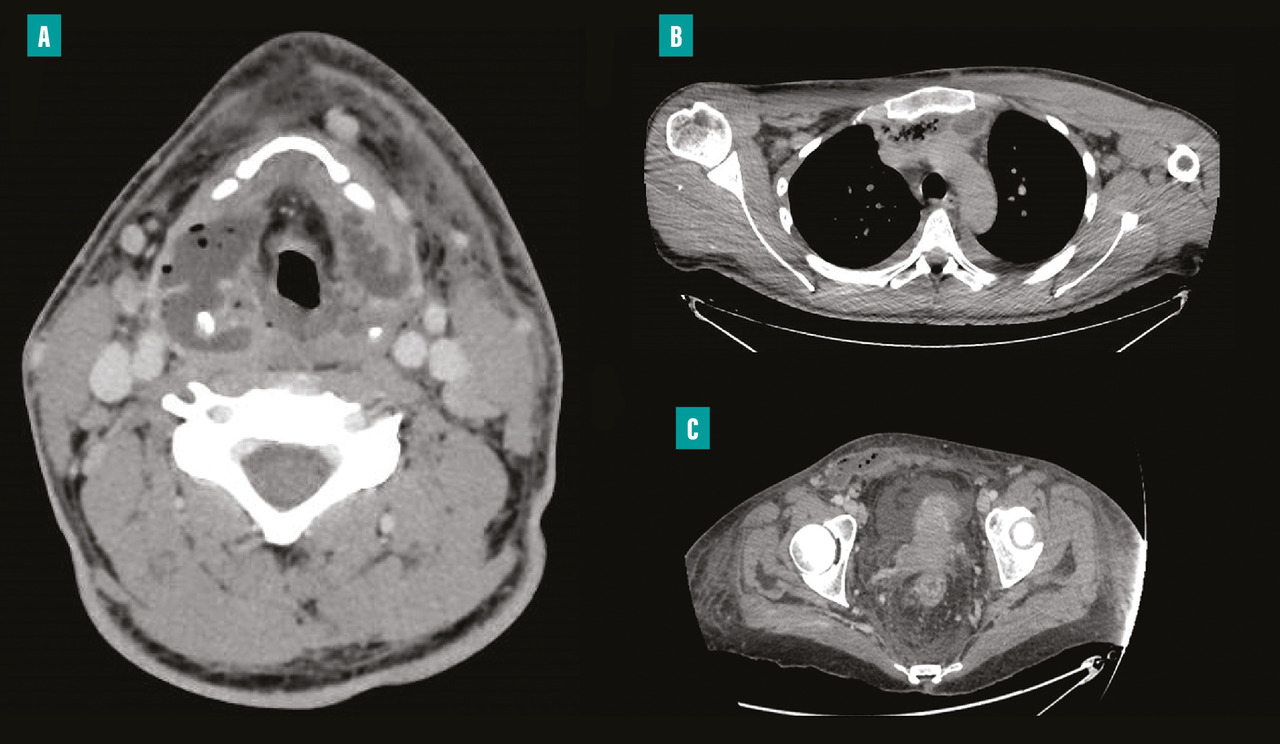

– la présence dans la majorité des cas d’une porte d’entrée à identifier et à traiter dès la phase initiale, avec une importance de l’imagerie pour guider le geste chirurgical (et non pour faire le diagnostic qui reste clinique) [fig. 2 ] ;

En effet, elles compliquent un foyer infectieux dentaire ou ORL dans respectivement 50 et 20 % des cas, avec une extension médiastinale secondaire objectivée chez 30 % des patients. Cette dernière doit être systématiquement recherchée car elle peut être à l’origine de complications nécessitant dans quelques cas un abord chirurgical thoracique (fig. 2 ).2 Enfin, une thrombose jugulaire n’est pas rare et doit être recherchée sur les examens d’imagerie, en premier lieu un scanner avec injection, afin d’associer un traitement anticoagulant à l’antibiothérapie.